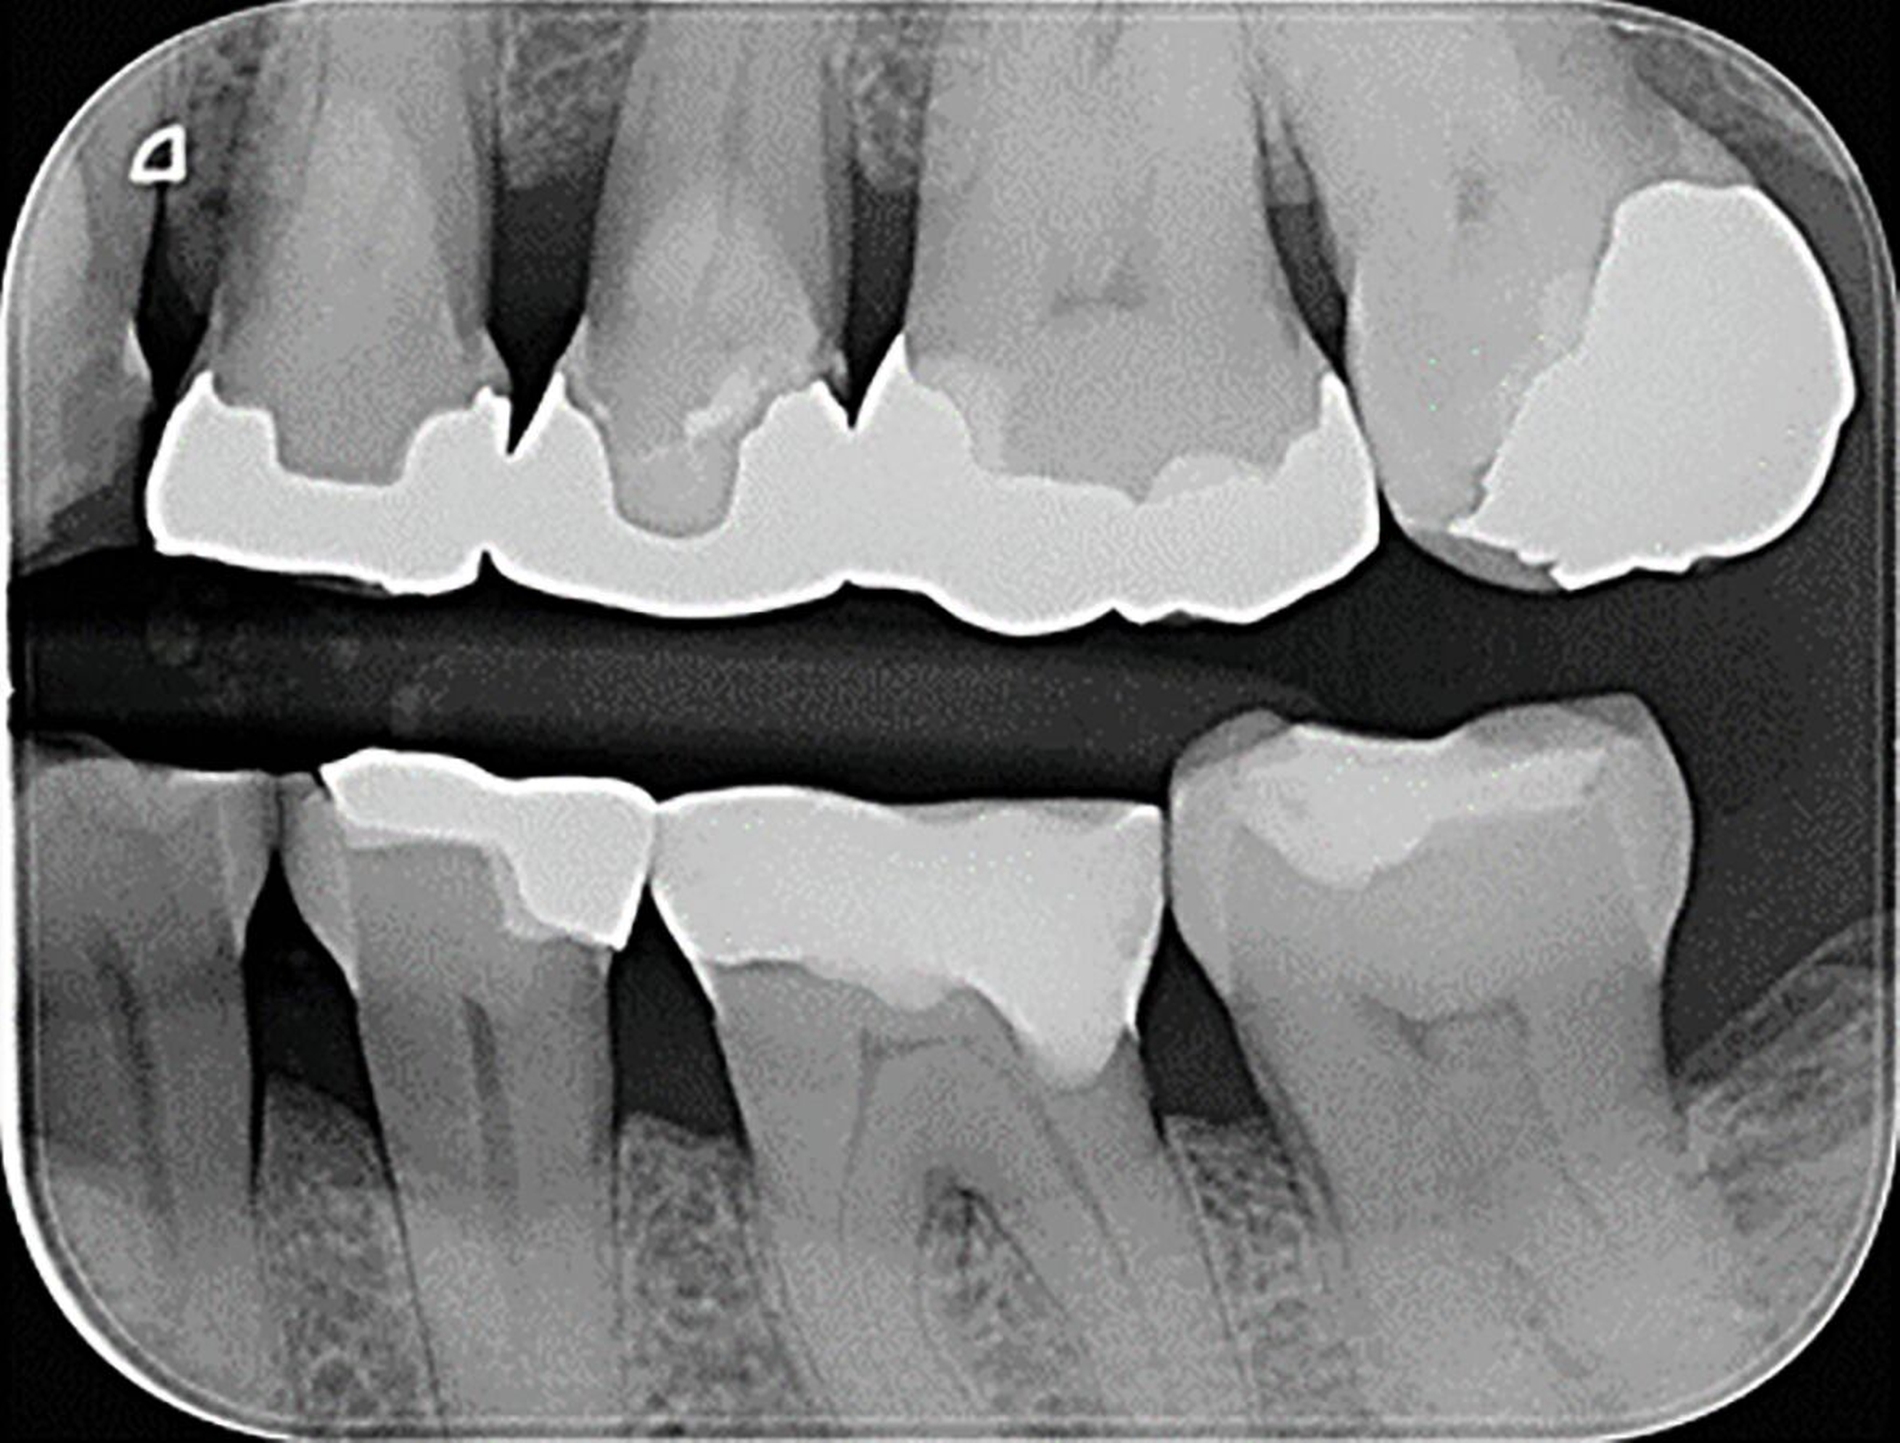

Aufgrund einer erwartungsgemäß erschwerten fotografischen Dokumentation bei der zahnärztlichen Behandlung in der mobilen Zahnmedizin wird die klinische Falldokumentation an einer Seniorin vorgenommen, deren Therapiefähigkeit und Eigenverantwortlichkeit nicht eingeschränkt war. Die 76-jährige Patientin stellt sich zur routinemäßigen Kontrolle in der Poliklinik für Zahnerhaltungskunde vor. Die allgemeine Anamnese ergab Zustand nach Meningeom, eine Quecksilber- und eine Birkenpollenallergie und einen erhöhten Blutdruck, der mit Lercanidipin eingestellt war. Am circa 20 Jahre alten Gussmetall-Inlay an Zahn 24 wurde dabei ein sondierbarer Randspalt festgestellt (Abbildungen 2a und 2b).